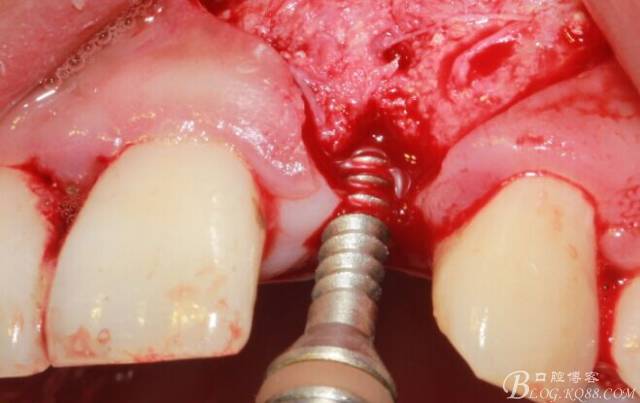

植入植體